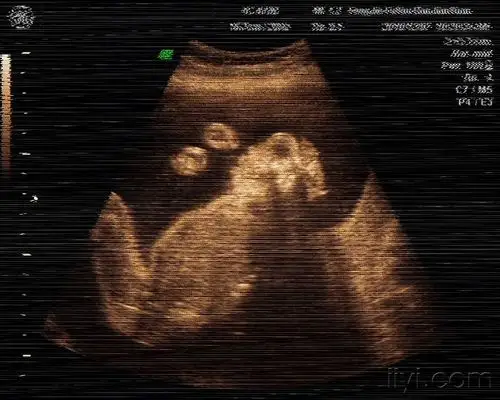

联体无脑儿 - 超声医学讨论版 - 爱爱医医学论坛

无脑儿 - 超声医学讨论版 - 爱爱医医学论坛